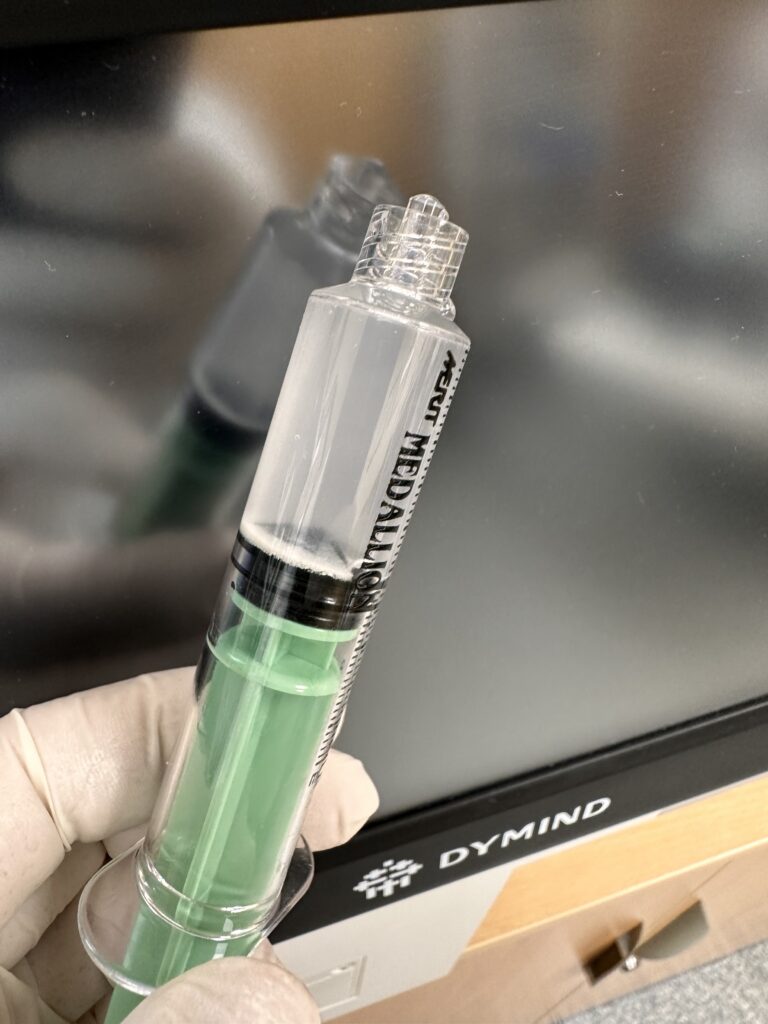

Actualmente se ha ampliado sus indicaciones para hacer tratamientos ecoguiados o ecoasisitidos para inyectar sustancias farmacológicas (anestésico, corticoides) o regenerativas (plasma rico en plaquetas, concentrado de médula ósea). O también para hacer procedimientos terapéuticos sencillos como eco-lavado de calcificaciones, evacuación de quistes sinoviales, neurolisis, tenolisis y un amplio abanico de posibilidades que podemos realizar los traumatológos y médicos deportivos.